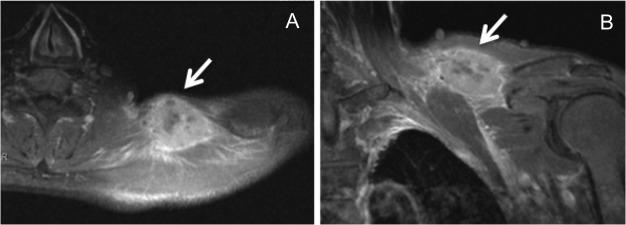

Cases of skeletal muscle metastasis of esophageal carcinoma are very rare, with few reports of long-term survival. We report a case of long-term survival after surgical resection of skeletal muscle metastasis. A 56-year-old man with advanced esophageal cancer and early gastric cancer underwent thoracoscopic esophagectomy, 2-field lymph node dissection, partial gastrectomy and gastric tube reconstruction. Six months later, cervical lymph node metastasis and mediastinal lymph node recurrence were found. Therefore, the patient underwent cervical lymph node dissection and adjuvant chemoradiotherapy. Two years and 3 months after the esophagectomy, a muscle metastasis was found in the left shoulder, and he underwent tumor dissection, followed by adjuvant chemotherapy for a year. There has been no sign of recurrence since, even 13 years after the esophagectomy. We believe our aggressive surgical treatment might have led to long-term survival.

食管癌骨骼肌转移病例非常罕见,关于长期生存的报道很少。我们报告一例骨骼肌转移瘤手术切除后长期生存的病例。一名56岁男性,患有晚期食管癌和早期胃癌,接受了胸腔镜下食管切除术、二野淋巴结清扫术、部分胃切除术和胃管重建术。六个月后,发现颈部淋巴结转移和纵隔淋巴结复发。因此,患者接受了颈部淋巴结清扫术和辅助放化疗。食管切除术后两年零三个月,左肩部发现肌肉转移瘤,随后他接受了肿瘤切除术,接着进行了一年的辅助化疗。自那以后,甚至在食管切除术后13年,都没有复发迹象。我们认为积极的手术治疗可能是导致长期生存的原因。